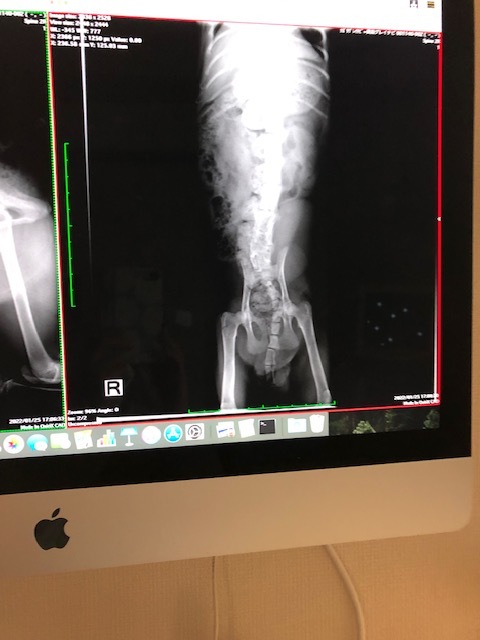

CT,MRIにむけてレントゲンを撮りました。

567がくっついている。やはりCT,MRIの必要が・・・というお話でした。

香川県の病院を紹介していただきまして現在日程の調整中です。